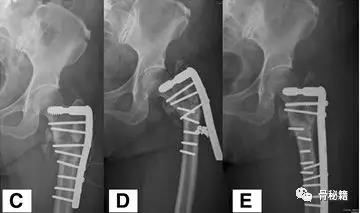

更换了DCS+植骨固定,术后四个月又发现了内固定失效再次更换了更长的DCS

这次的固定能成功吗?